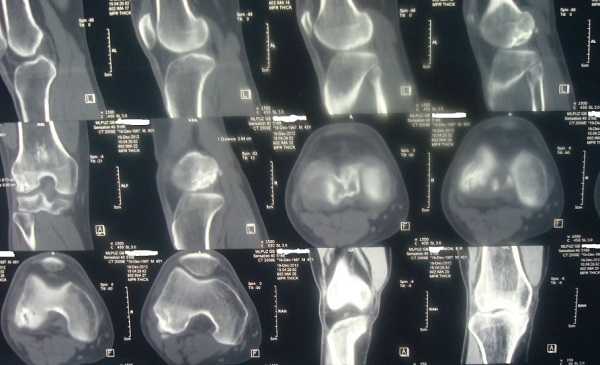

КТ коленного сустава - это метод рентгенологической диагностики, которая в медицинских клиниках СПб осуществляется на низкодозных спиральных компьютерных томографах со срезовой мощностью от 12 до 320 срезов. Данная томография относится к быстрым способам исследования. Сканирование занимает всего 3-5 минут, а его расшифрованные результаты доступны в течение 30-40 минут с момента проведения. Сама диагностика проводится неинвазивно, безболезненно и в комфортных условиях для пациента. Средняя лучевая нагрузка на организм составляет 2-3 мЗв, что, в случае необходимости, позволяет делать МСКТ колена 1-2 раза в год без угрозы для здоровья.

- созданием трехмерной модели сустава;

Процедура МСКТ коленного сустава проводится в закрытом помещении, где установлен мультиспиральный компьютерный томограф. От мощности томографа зависит толщина шага сканирования. Некоторые аппараты могут делать послойные срезы-снимки с минимальным шагом в 0,5-1 миллиметр. Мощность аппарата определяется срезовостью томографа, которая варьируется от 12 до 320 срезов. Чем выше этот показатель, тем качественнее будут полученные снимки, и, соответственно, цена КТ колена тоже будет выше.

Сама процедура проста и длится около 5 минут. Пациента помещают на томографический стол, который заезжает внутрь специального кольца сканера. Трубка томографа совершает движения вокруг выбранной области, во время каждого оборота производится серия снимков.